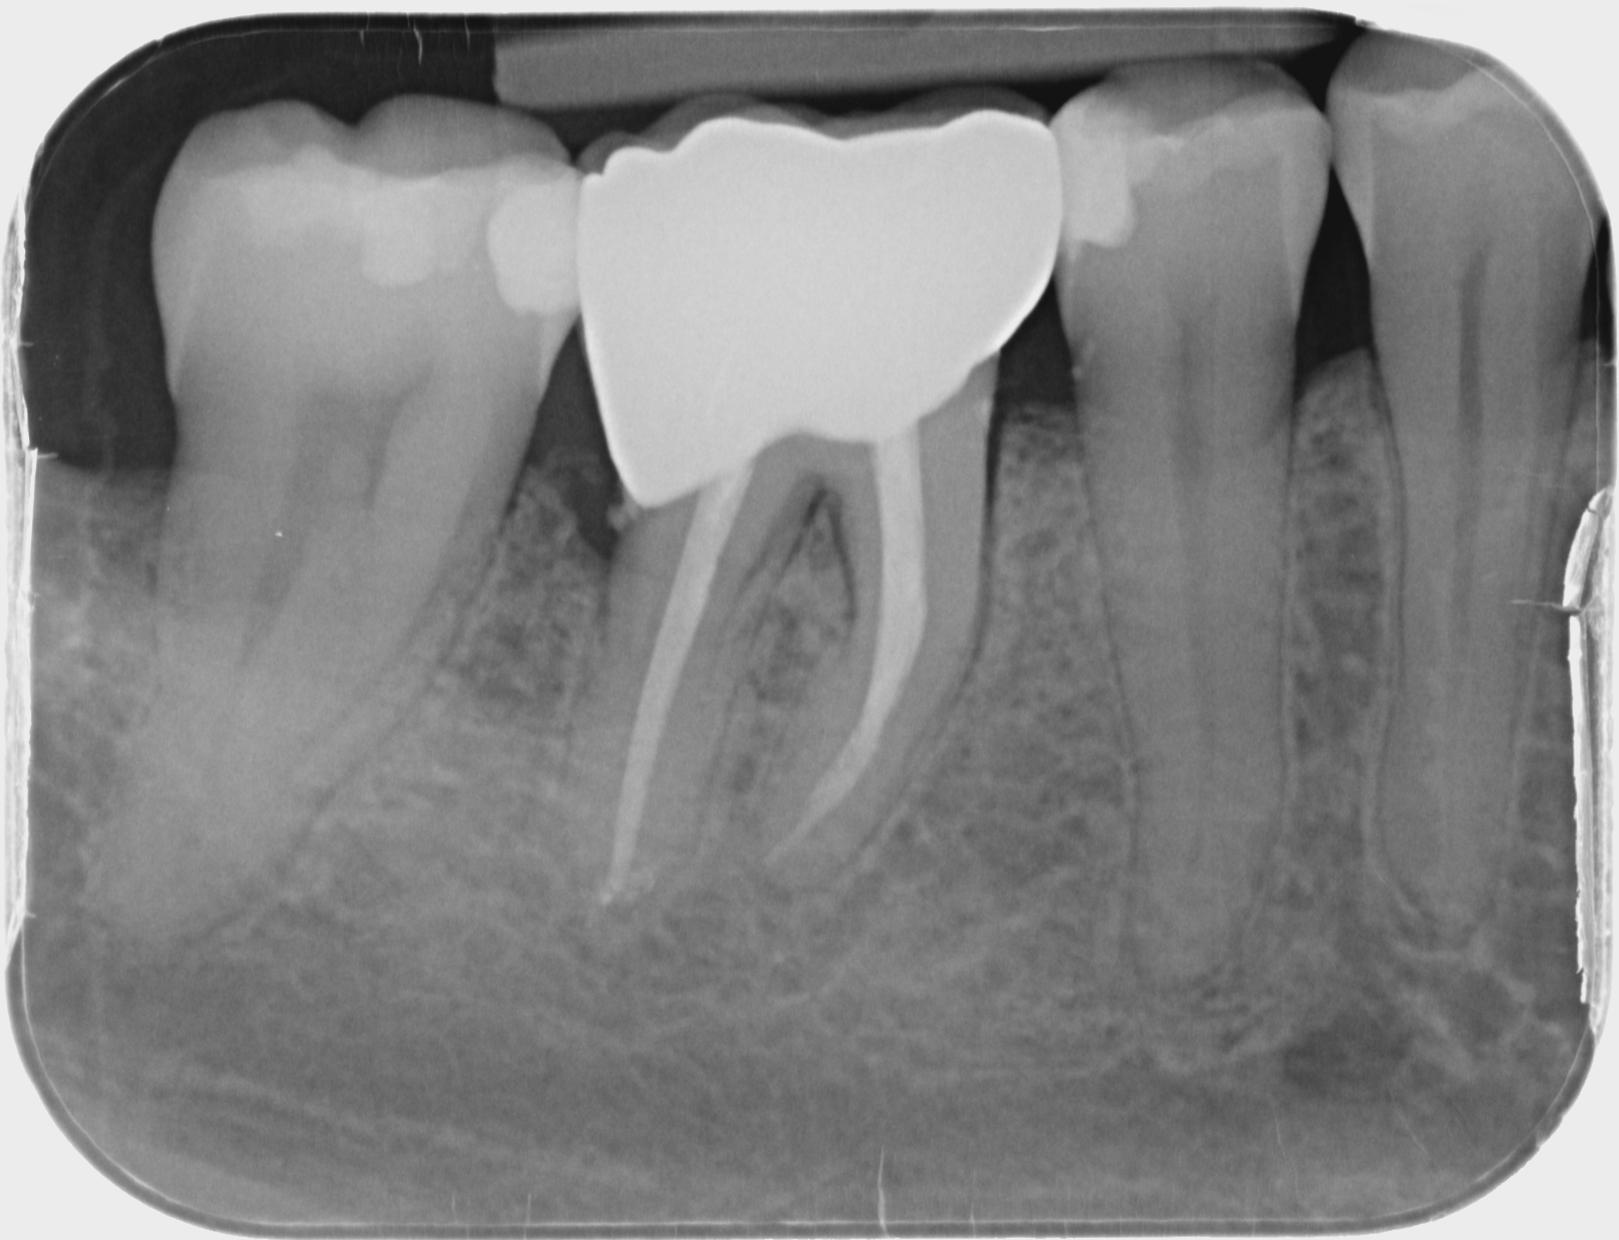

- Voruntersuchung: Gründliche Untersuchung und Röntgenaufnahmen zur Beurteilung des Zahns.

- Wurzelfüllung: Die Kanäle werden mit einem biokompatiblen Material verschlossen.

- Verschluss des Zahns: Der Zahn wird mit einer Füllung oder Krone verschlossen, um Stabilität zu gewährleisten.